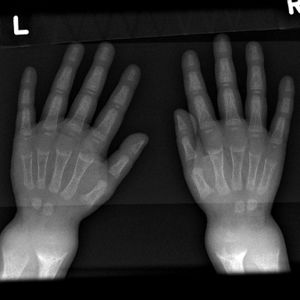

| تصوير بالأشعة لمريض بالرخد في الثانية من عمره، with a marked genu varum (bowing of the femurs) and decreased bone opacity, suggesting poor bone mineralization. | |

- شعاعياً: يكون التشخيص الباكر للرخد الفعال أفضل ما يكون في المعصم، لأن التبدلات المميزة في نهاية الزند والكعبرة تحدث في المراحل الباكرة. تتسمك المنطقة الغضروفية ويزداد عرض النهاية البعيدة لجسم العظم، فتبدو متسعة ومقعرة ومهترئة وتنقص كثافة جسم العظم.